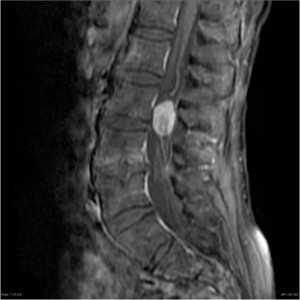

4. МРТ при остеохондроме:

• Нормальный костный мозг, распространяющийся в экзостоз

• Кортекс неразрывно связан с подлежащей костью

• Волнообразная крышка из гиалинового хряща у взрослых не превышает 1 см по ширине:

о Крышка характеризуется дольчатым сигналом высокой интенсивности в последовательностях, чувствительных жидкости (в режиме Т1 интенсивность сигнала от низкой до средней)

о Крышка покрыта тонкой надхрящницей, характеризующейся сигналом низкой интенсивности в режимах Т1 и Т2

о У молодых, активно растущих пациентов нормальный хрящ характеризуется другими признаками:

- Может быть до 3 см толщиной

- Отчетливая неоднородность во всех последовательностях

• Минерализованные зоны в структуре крышки и экзостоза сохраняют низкоинтенсивный сигнал во всех последовательностях

• Накопление контрастного вещества ограничено тонкой фиброзно-васкулярной тканью, покрывающей (не накапливающую) хрящевую крышку и тонкой перегородкой в структуре крышки

• Мягкотканный компонент отсутствует